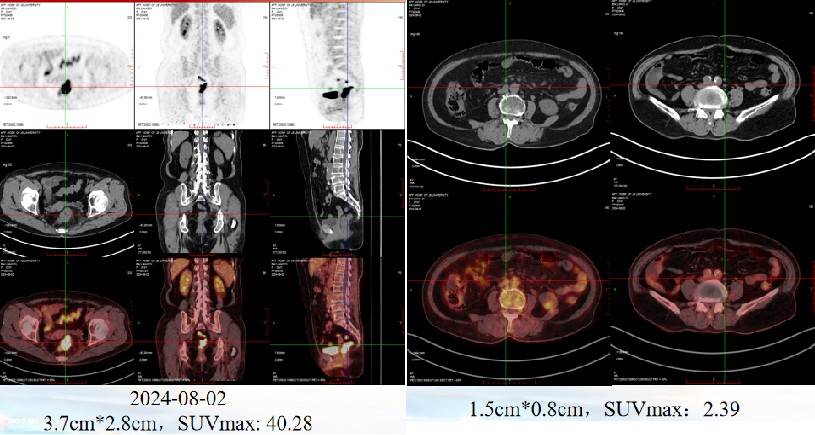

2024年8月2日行PET-CT检查:1、直肠壁不均匀增厚伴FDG代谢增高,符合直肠Ca表现。2、病灶周围及双侧盆壁小淋巴结伴FDG代谢增高,考虑转移。3、腹腔及腹膜后散在淋巴结,FDG代谢轻度增高,部分转移待排。

疗效评估:2024年10月30日复查CT及MRI,影像评估提示病灶较前明显缩小(肿瘤缩小43%,盆腔淋巴结退缩),疗效评估为部分缓解(PR)。